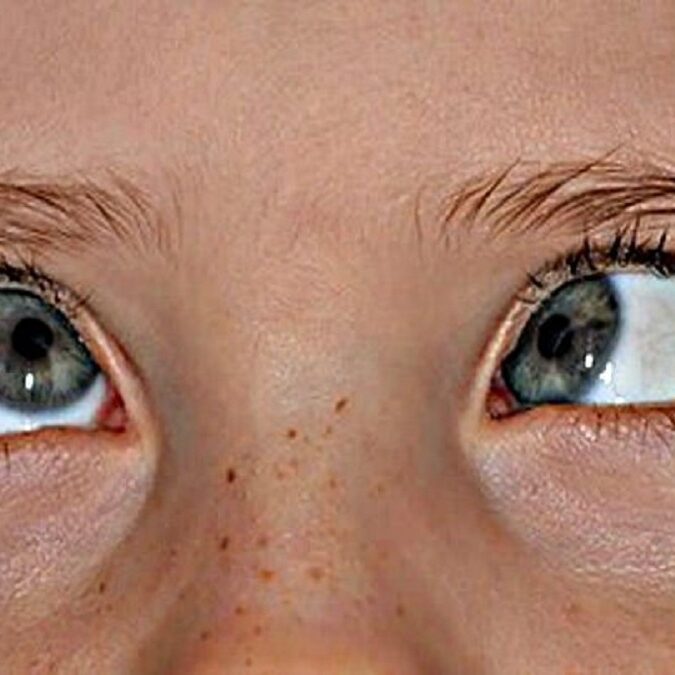

SÍNDROME DE DUANE O ESTRABISMO CONGÉNITO

El síndrome de Duane es un trastorno del movimiento ocular poco común. Por lo general, los niños con síndrome de Duane reciben el diagnóstico a la edad de 10 años, aunque está presente desde el nacimiento.

El síndrome de Duane afecta los músculos que controlan el movimiento del ojo. En todos los casos, una persona con síndrome de Duane tendrá poca o ninguna capacidad para mirar hacia afuera (hacia sus oídos) y, a menudo, tendrá una capacidad limitada para mirar hacia adentro (hacia su nariz).